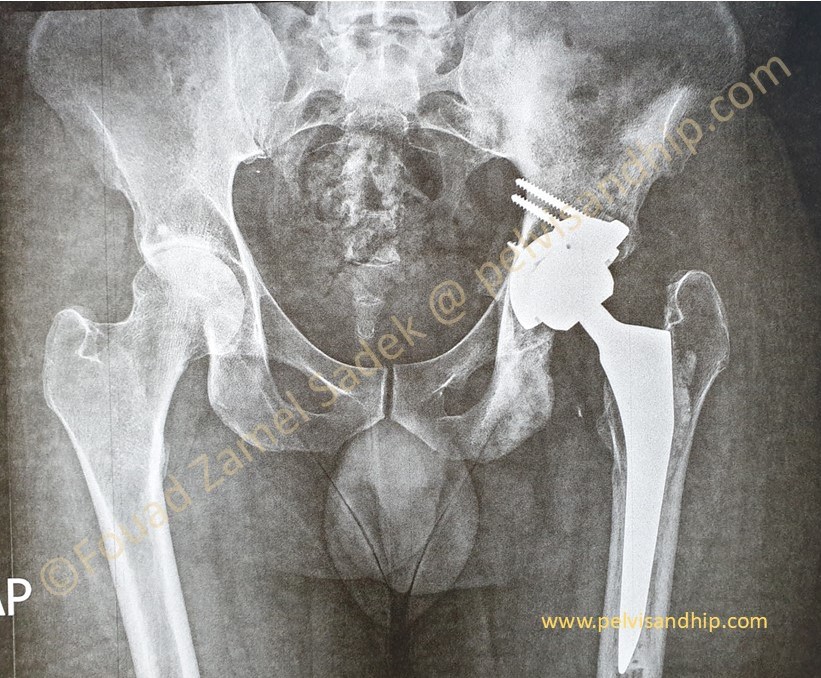

Through a posterior approach, the true acetabulum was identified and cleared of all haling tissues and debris. Radical releases including the postero superior as well as the inferior capsules were done. A periacetabular release procedure was carried out with additional releases of the gluteal maximus attachment into the gluteal tuberosity of the femur. A superior trabecular metal augment was applied as per routine. A porous coated cementless spherical cup was inserted close to the TAL. No further grafting was needed.

A cemented stem was chosen due to very poor quality bone withing the metaphysis of the femur and for that a cemented option for the femoral stem was chosen. The leg length adjusted as per immediate postoperative finding. At the last follow up, patient is walking with no support. He has a very reasonable abduction function. He has returned to work with good satisfaction. Still working on improving his abduction function.